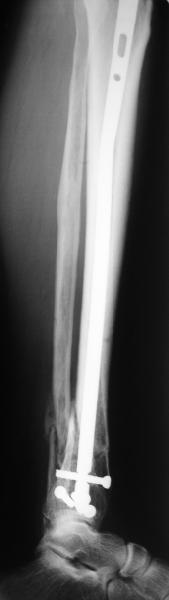

At least both the ankle mortise and tibial alignment look acceptable, don't they?

I am just trying to illustrate that prevention of 1)tibial valgus and 2)loss of reduction can be provided without fibular plating. Small changes of conventional nailing techniques allow to maintain reduction of the tibia reliably without adjunctive fibular stabilization.

In delayed cases acute length restoration performed only in the tibia may leave the fibula shortened thus change the mortise. So it is reasonable to restore length of both bones simultaneously by distractor and fix the fibula not with open reduction and plating but just by a single perQ screw. Example attached.